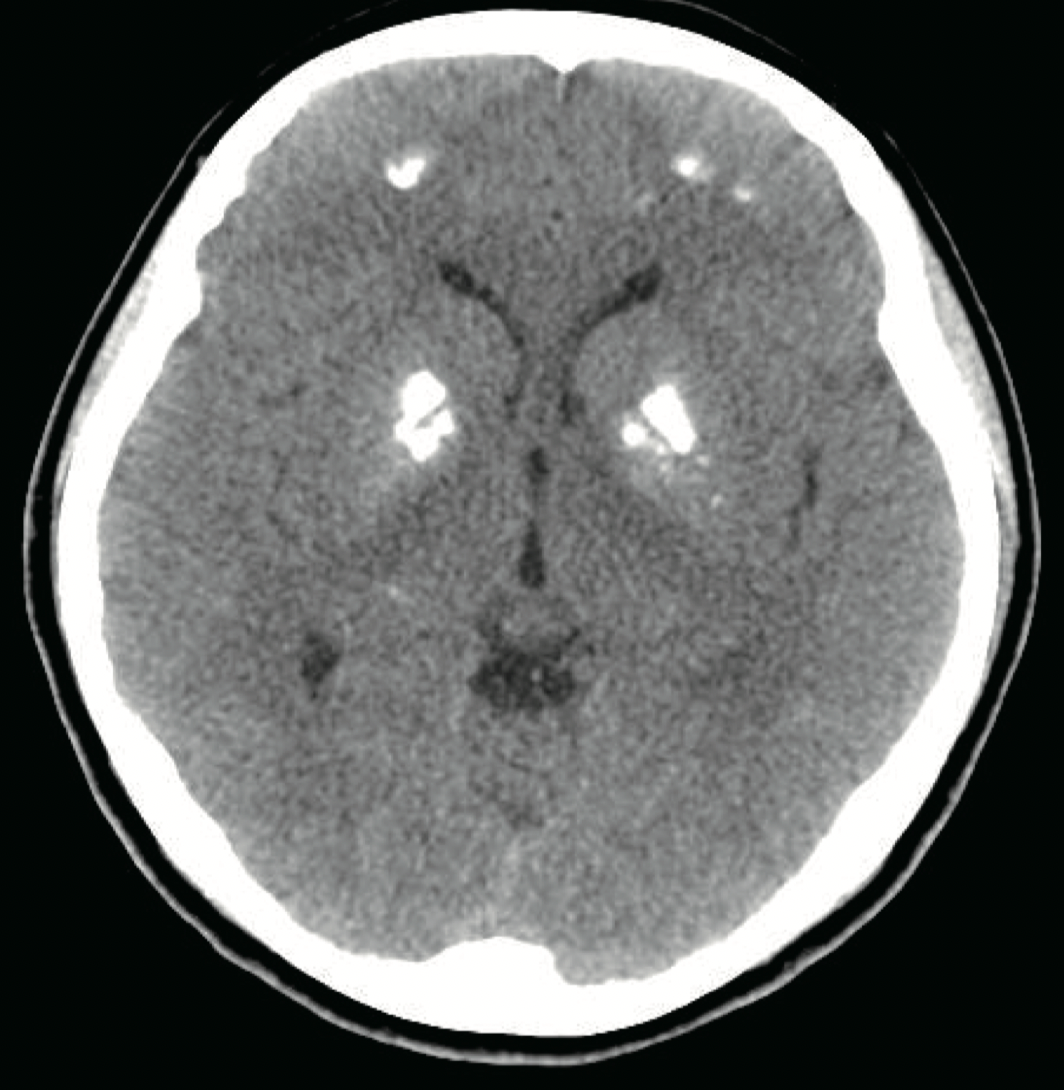

At 15 years old, the patient visited hospital complaining of dizziness, nausea, and vomiting. Her serum calcium level was 18.4 mg/dL and her serum potassium 2.8 mg/dL. Calcification of the subcortical and basal ganglia of both frontal lobes was found on brain computed tomography (Figure). Her medication at admission was calcium acetate, alfacalcidol, hydrochlorothiazide, and amiloride. A month before the second hypercalcemic episode and the dose of alfacalcidol had been increased because her serum 25-hydroxy-vitamin D3 (25-OHVitD3) concentration was just above the lower limit of the normal range. All medication was discontinued and her serum calcium and potassium concentrations gradually normalized, but because of persistent dizziness she was transferred to our hospital. On the day after transfer, she complained of paresthesia of her hand and her serum calcium concentration was 8.2 mg/dL. Alfacalcidol and calcium carbonate were administered and the dose of medication was slowly increased . Alfacalcidol was changed to calcitriol and she was discharged.